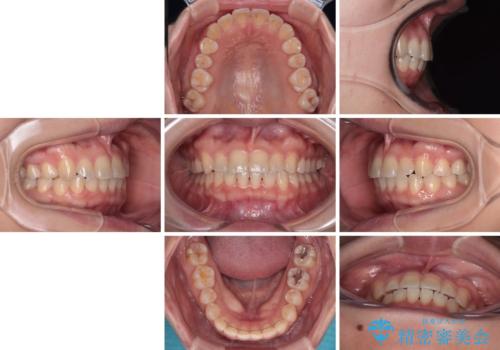

八重歯を治す 非抜歯のワイヤー矯正治療

- 左右の八重歯を気にして来院された患者様です。

ワイヤー装置でもマウスピースでも対応可能な歯列でしたが、マウスピース矯正は自己管理が煩わしいとのことでワイヤー矯正を選択されました。

八重歯である犬歯は歯根が長いため、上顎前歯が出っ歯になるリスクがあるため、必要に応じてアンカースクリューを用いて奥歯を後方に移動させる可能性をお伝えしました。

舌の突出癖により上下前歯が開咬となりましたが、舌のトレーニングと顎間ゴムの使用により、元々の被蓋関係に改善することができました。

アンカースクリューを用いて、出っ歯仕上がりを回避し、正中位置も改善することができました。